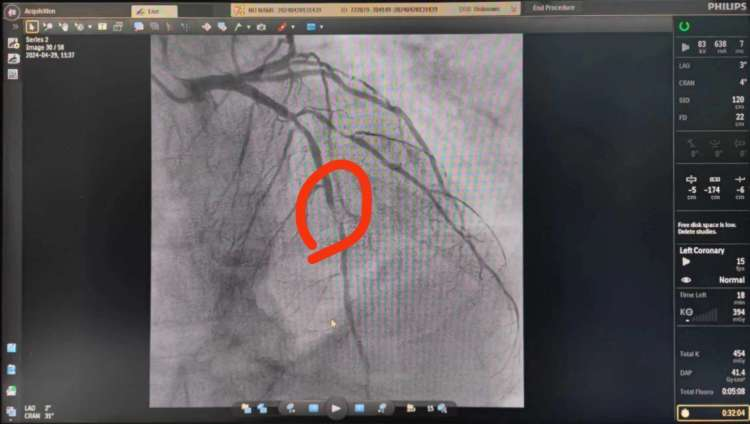

手术取栓成功